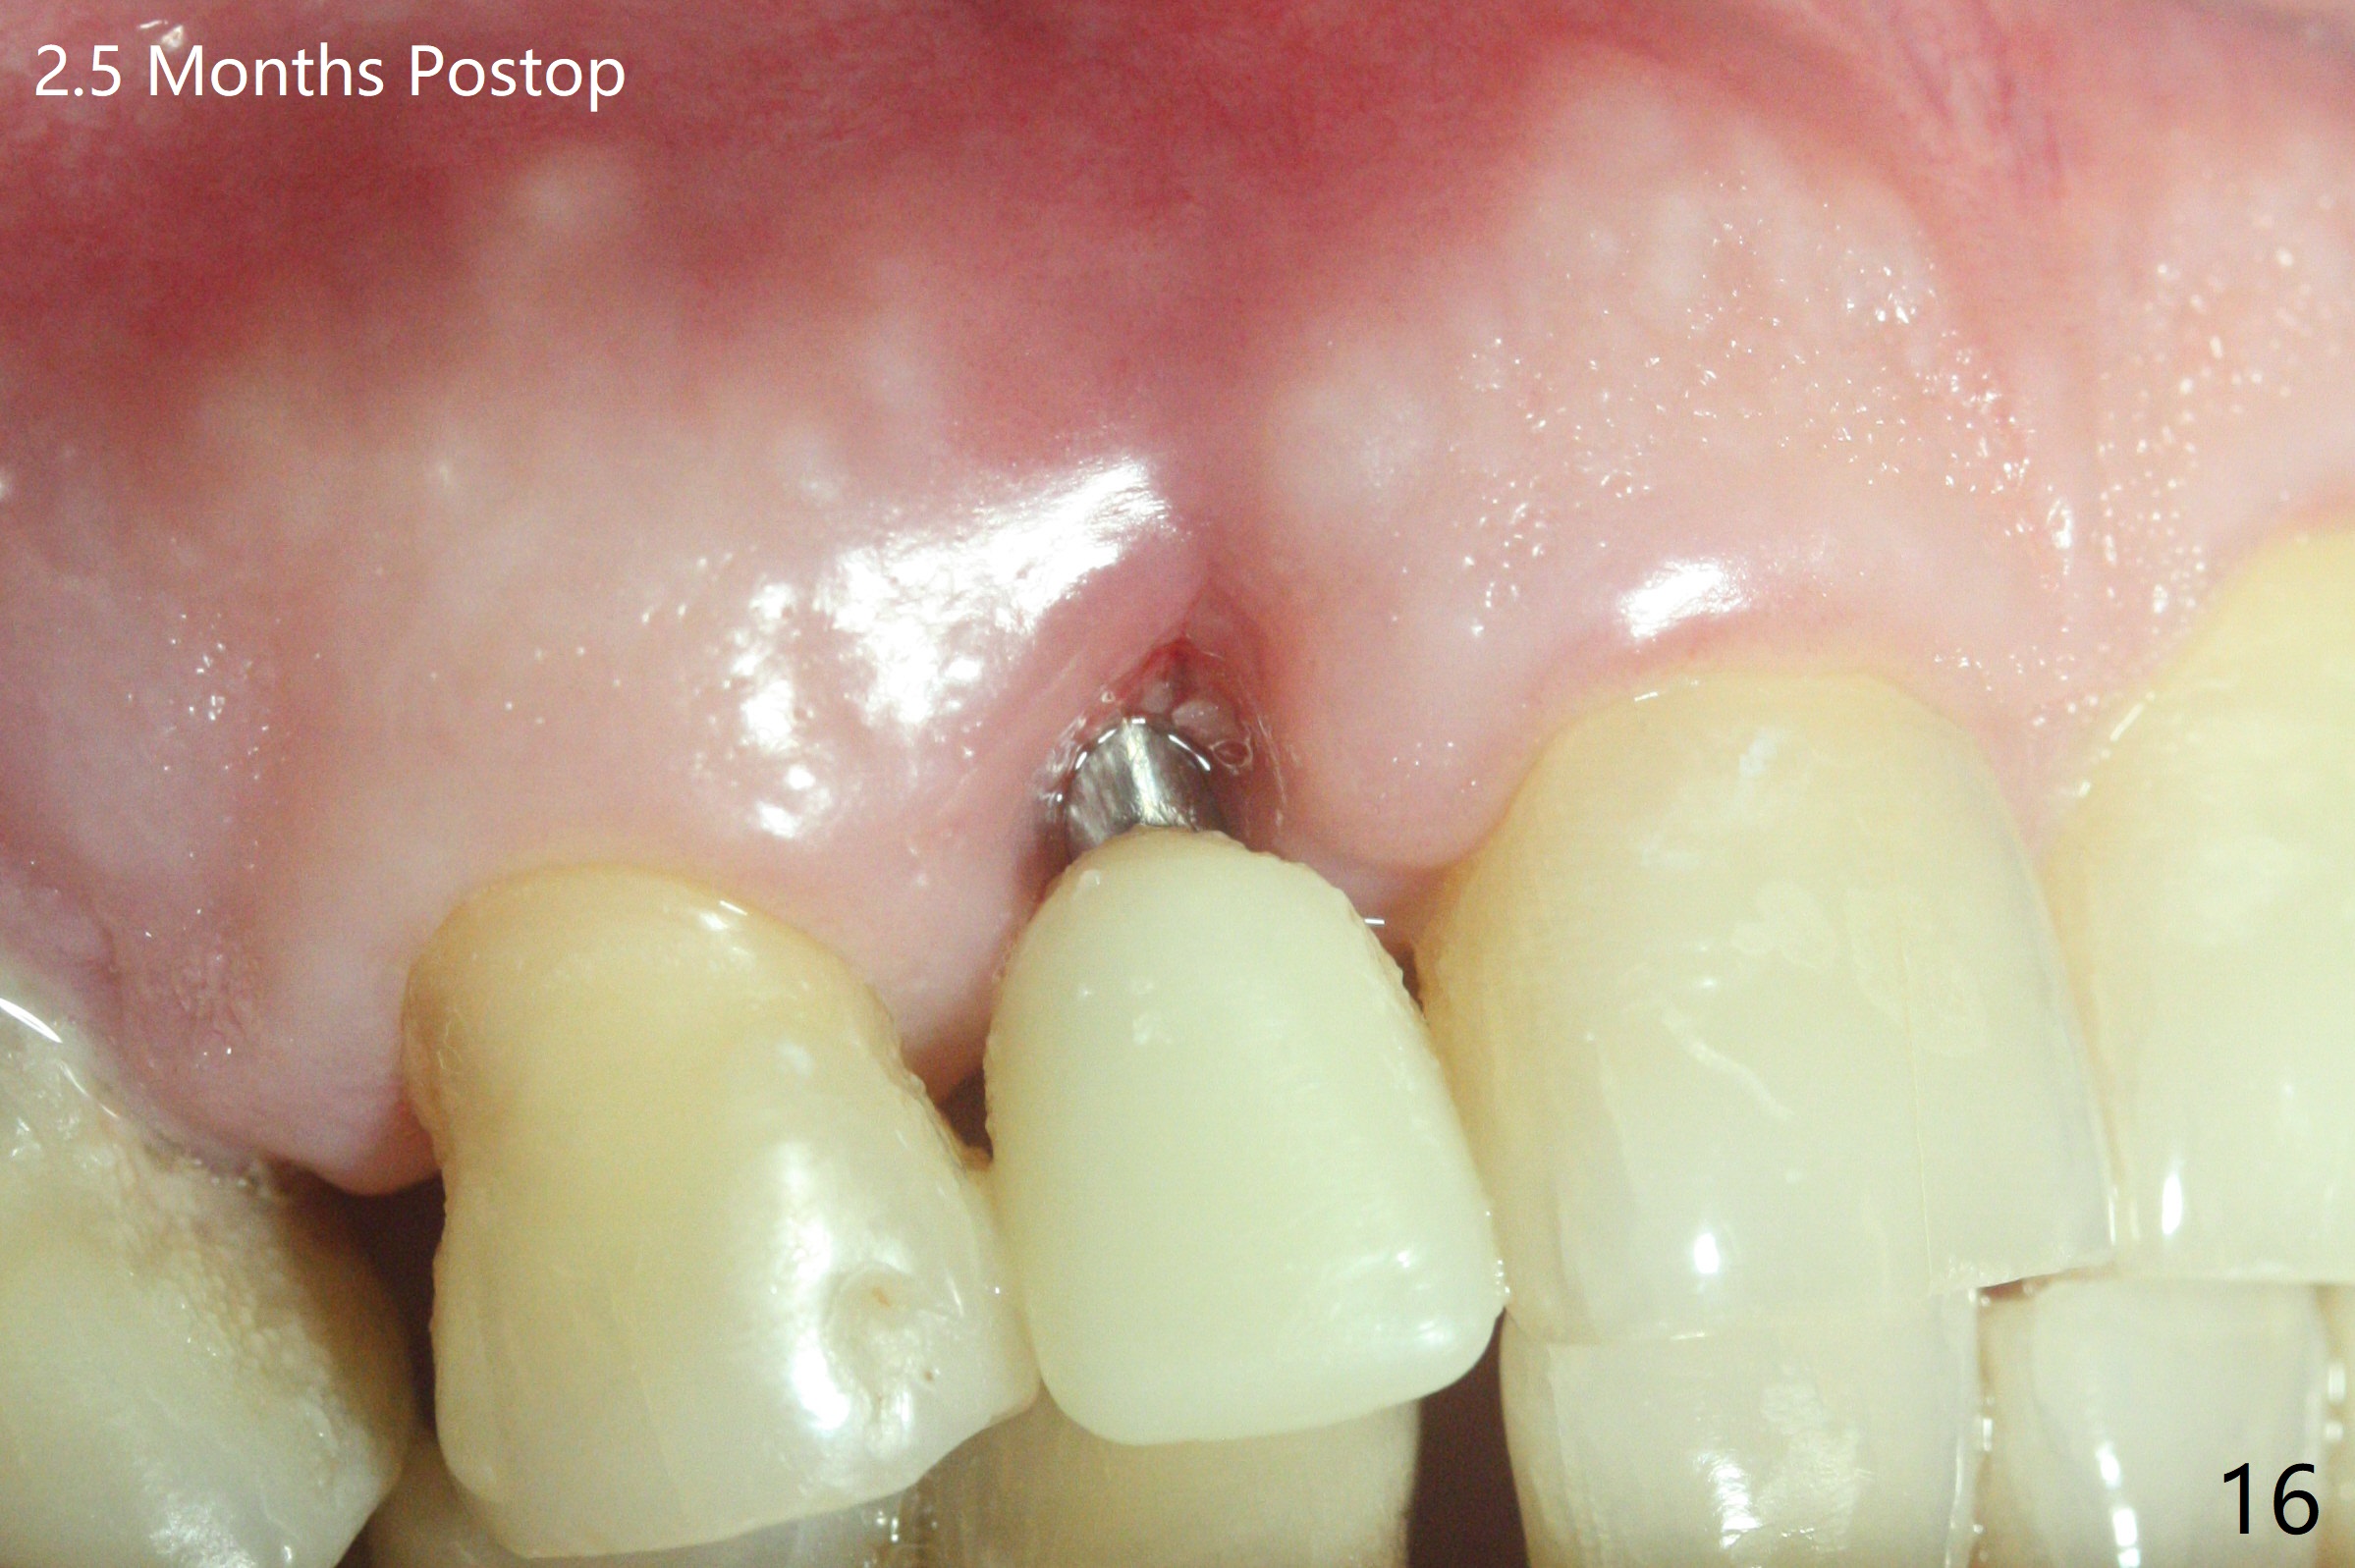

68岁男士右上2严重骨质吸收,颊侧骨板缺失,术前牙龈退缩也十分明显(图一,二),术中对脆弱牙龈缘(图三:*)不应施加任何压力或者牵拉,更不能切开,保持最佳血供。按照术前设计,在牙槽窝腭侧钻洞(图四),植入2.5x15毫米一段式植体(扭力>35Ncm),基台特长(牙龈厚,图五)),基台位于合适修复位置(图六),4-5毫米螺纹颊侧暴露(图七:*)。植骨(图八(CT冠状切面(拔牙后:黑色)):箭头)前,将PRF膜(白线)一头(a)插入牙槽窝颊侧,另外一头(图八,九:b)放置颊侧牙龈颊侧。然后填入粘性骨粉(图九:S;图十四:*),将b头PRF膜往下翻,它末端事先冲一个洞(punch a hole using sterilized rubber dam punch),插入基台(图十(粉红色),十一),这样PRF膜不移位,牢靠地固定骨粉(图十(红圆圈),图十四:*),最后使用树脂敷料覆盖伤口(图十二,十三:A),同样需要基台(箭头,也就是一段式植体)固定,也就是没有即刻植体,就没有骨粉固位。术后两个月伤口缩小,肉芽组织生长(图十五)。撤除树脂敷料后,制作临时牙冠,半个月后唇侧植体有些暴露(图十六),嘱咐强化口腔卫生。